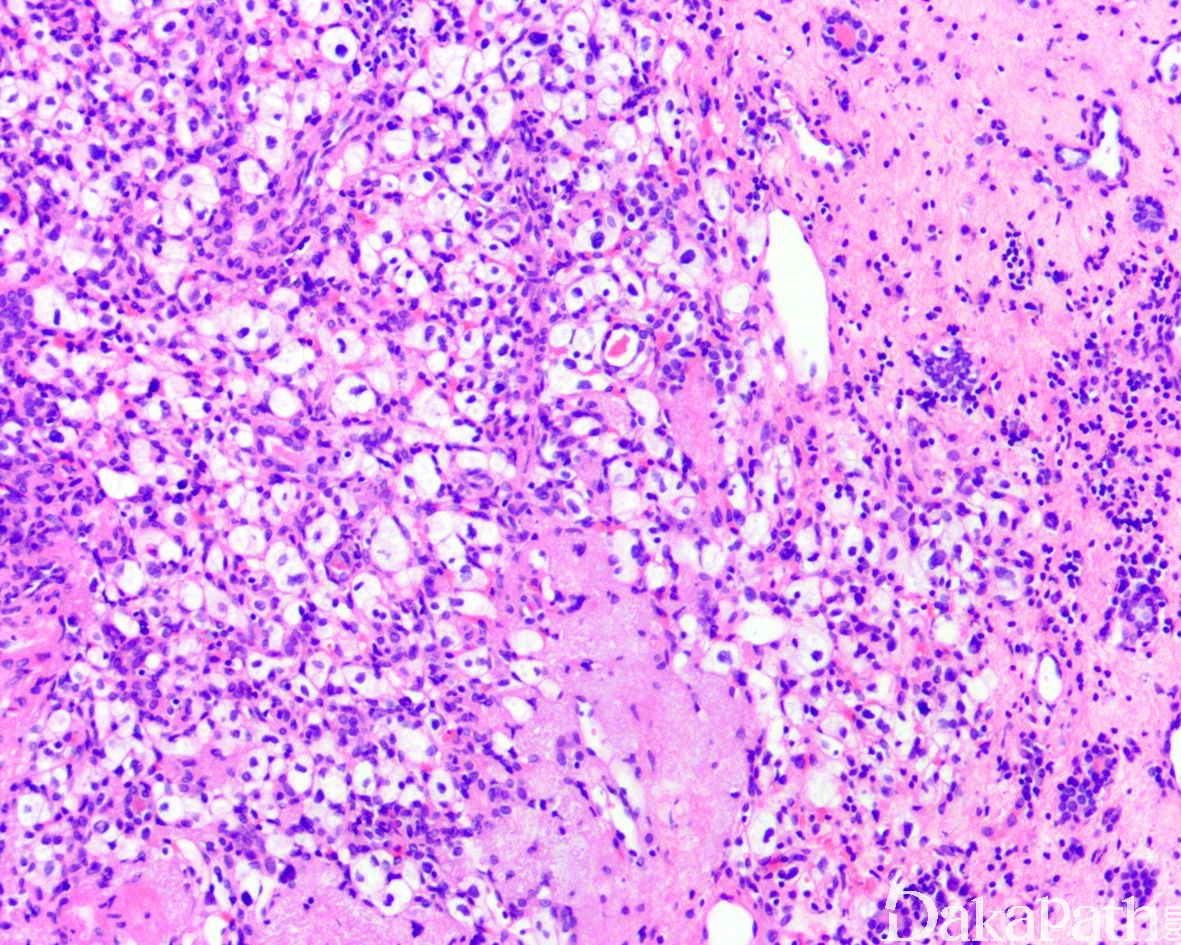

形态学类似于中枢神经毛细血管血管母细胞瘤,由间质细胞和大量毛细血管构成。

肿瘤与周围肾组织分界清楚,边缘可见内陷的肾小管,肿瘤间质血管丰富,分支血管网间可见卵圆形瘤细胞呈片状、或分叶结节状增生,局部可见瘤细胞围绕血管呈放射状排列;

细胞胞浆淡染或嗜酸性,胞浆内多泡状淡染脂质空泡,有些病例可见横纹肌样细胞形态,也可见大的嗜酸性小球和局灶的钙化;

大多数病例细胞仅轻微多形性,偶尔可见怪异细胞。

偶尔可见血管母细胞瘤成分与透明细胞肾细胞癌成分混合,提示两者可能是不同分化阶段的谱系肿瘤。